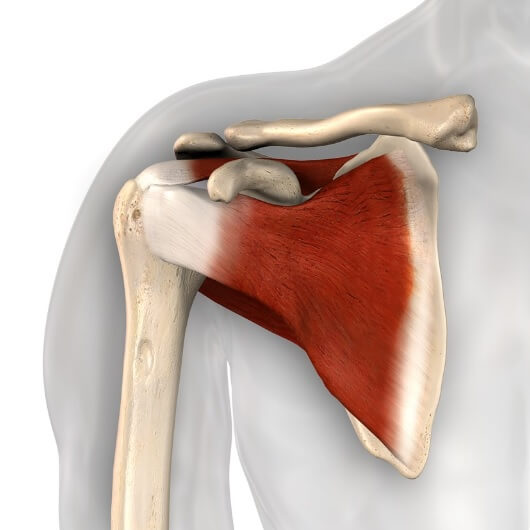

Фотографии мышц ротаторной манжеты плеча